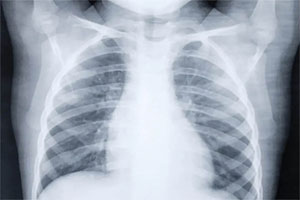

Pochi sintomi di Covid-19 o addirittura nessuno. Ma la radiografia del torace svela la realtà: la malattia si è fatta strada nei polmoni ed è visibile – bianco su nero – nelle ‘lastre’. Per la precisione, in 100 su 170 eseguite in una sola settimana; si è scoperto che Radiografia torace svela Covid in asintomatici.

n una sola settimana è stato riscontrato come 100 radiografie al torace su 170 – circa il 60% – presentavano immagini riconducibili a una polmonite interstiziale bilaterale, quindi altamente sospette e riferibili alla polmonite correlata a Covid-19. Il coinvolgimento era bilaterale in tutti i casi: simmetrico nel 54% dei pazienti, mentre le anomalie dei raggi X al torace erano maggiori su un lato del torace nel 46% dei casi.